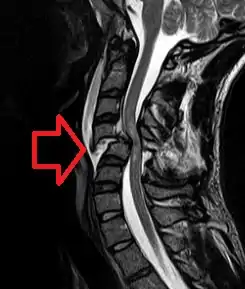

![]() МРТ перелому шийного відділу зі зміщенням зі здавленням спинного мозку. МРТ перелому шийного відділу зі зміщенням зі здавленням спинного мозку. | |